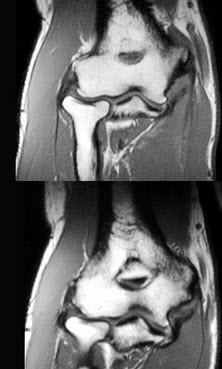

男,28岁,喜爱球类运动,内侧肘部疼痛3个月,结合图像,最可能的诊断是()

A .尺侧韧带撕裂

B .未见异常

C .桡侧韧带撕裂

D .肱骨远端骨折

E .尺骨骨折